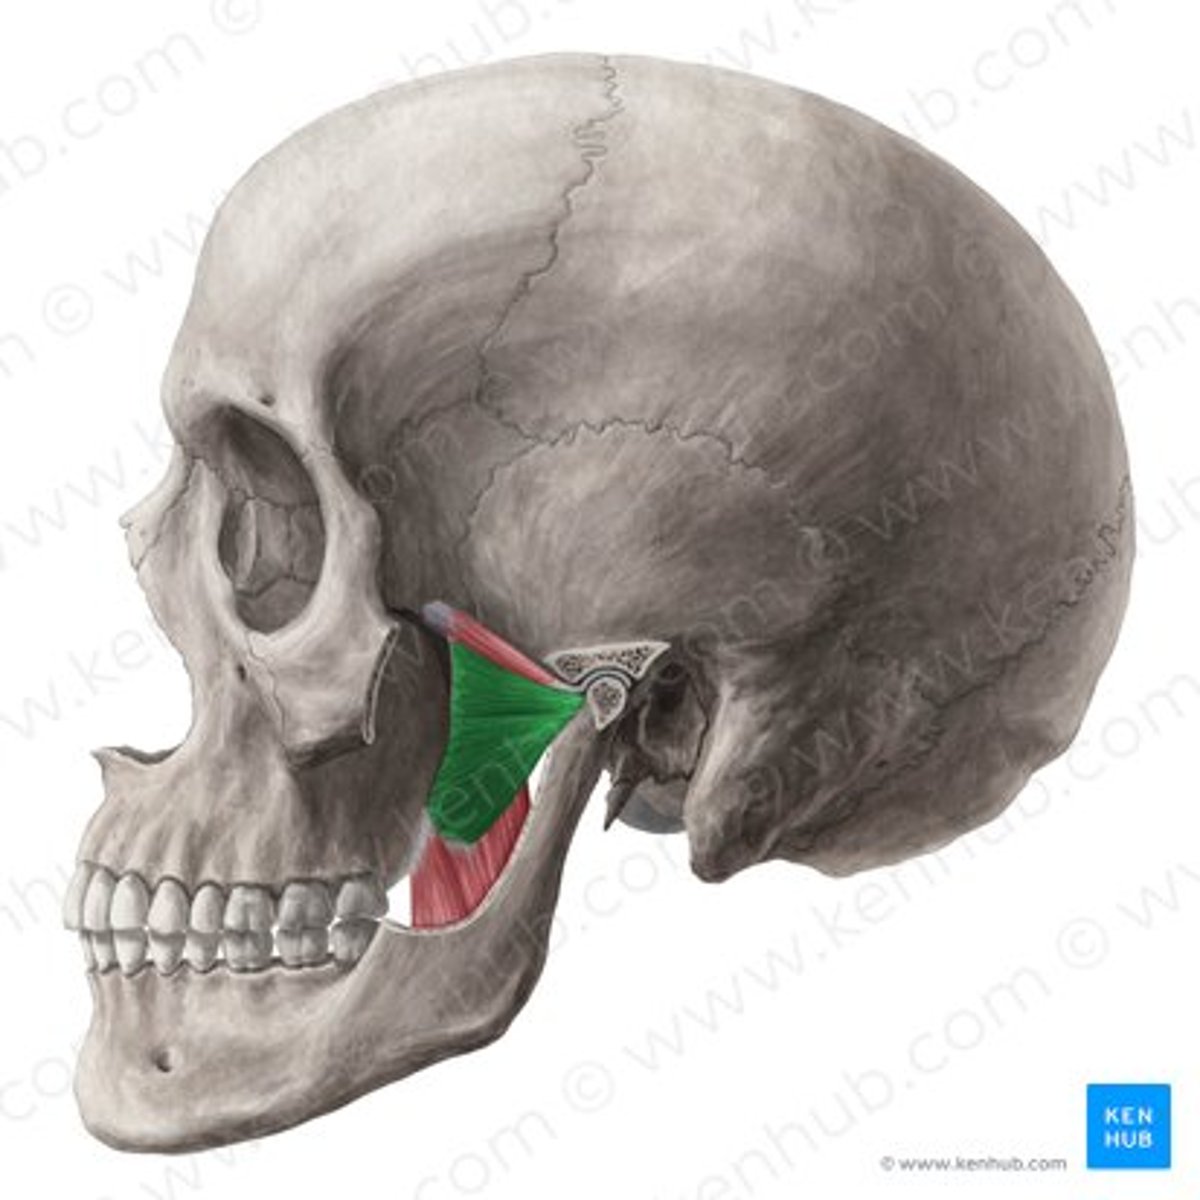

deep masseter

superficial masseter

temporalis

temporomandibular joint capsule

lateral pterygoid

coronoid process